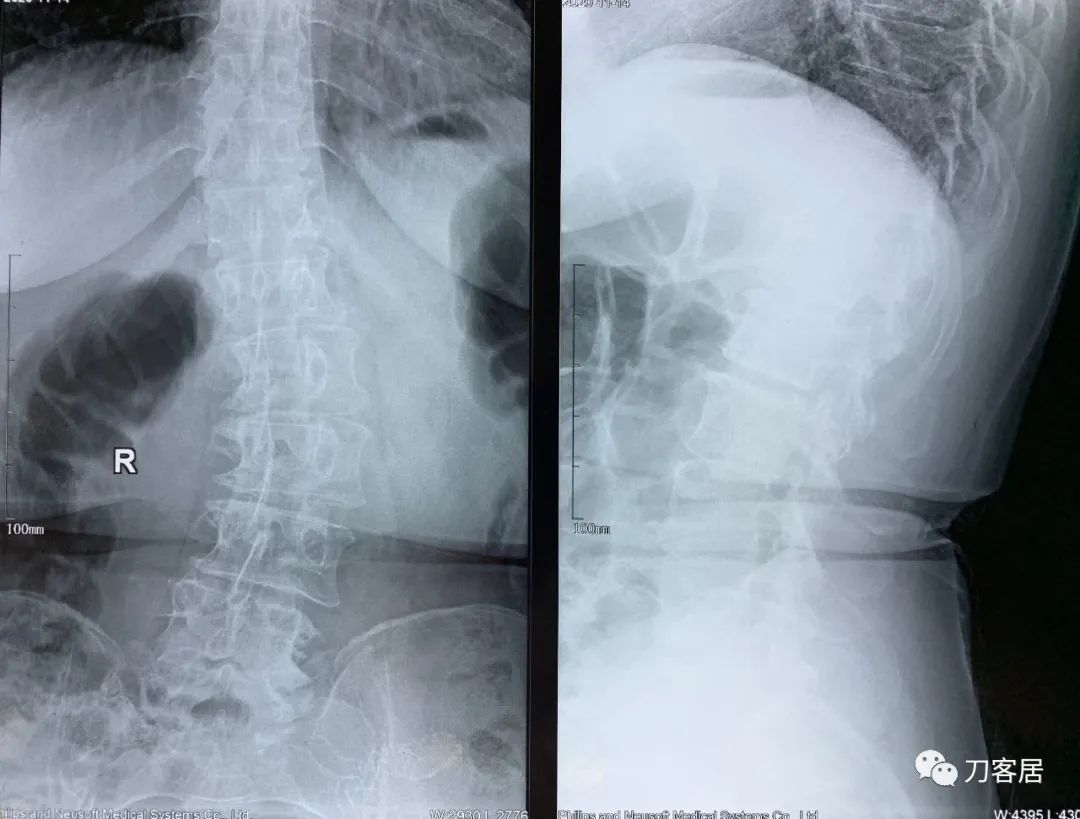

患者自2020年8月4日始头晕,2020年8月25日双手麻,双胳膊麻,于兰大二院定西分院检查颈椎MRI及腰椎X线片, 提示1. 颈椎生理曲度变直,2. 颈椎骨质增生,3. 颈椎间盘变性,颈4-7椎间盘轻度膨隆,4. 腰椎侧弯畸形。

2021年5月17日,西京医院骨科门诊找我就诊,自带影像学检查资料提示腰椎侧弯,腰3-4,腰4-5椎间盘突出,黄韧带肥厚,椎管狭窄。

建议其查双光子骨密度,骨盆正位片以及腰椎间盘平扫。腰椎正侧位X线片以及动力位片,站立位脊柱全长正侧位X线片,以了解其是否有骨质疏松,并了解脊柱侧弯情况,腰椎局部X线表现情况和腰椎间盘突出和椎管狭窄情况。

从这个患者的影像资料分析,颈椎间盘突出问题不大,没有明确的上位神经元损伤表现,所以,不考虑颈椎和胸椎问题。腰椎侧弯畸形,但不严重。因为存在腰椎侧弯,使得腰椎MRI在扫描切面的时候,显示的椎间盘突出或椎管狭窄会有一定的误差,所以,又加做了经椎间盘的CT平扫,影像表现并不严重,综上,腰椎间盘突出,腰椎管狭窄,腰椎侧弯,不考虑手术治疗。同时,患者的主要痛苦是心理疾病,而不是器质性疾病,所以,以心身疾病治疗为主。虽然患者骨密度检查结果提示正常,但X线片显示骨质疏松,且其症状也与骨质疏松的症状有符合之处,比如静息痛,不能入睡,动作及姿势变换时痛加重等,所以,给予实验性抗骨质疏松治疗,以观疗效。